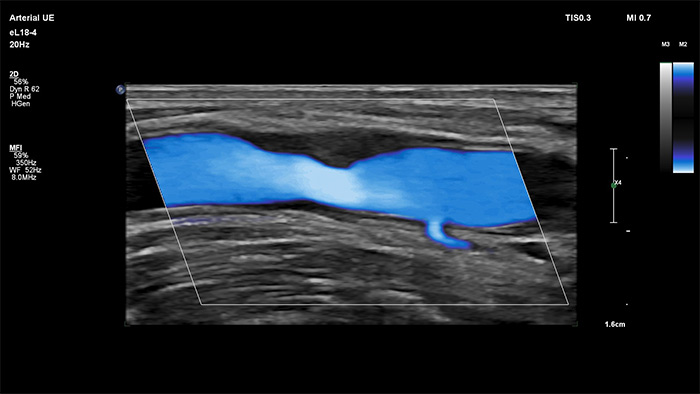

O MicroFlow Imaging da Philips foi concebido para detetar fluxo sanguíneo lento e fraco nas estruturas anatómicas do tecido com uma sensibilidade notável e melhorar a resolução do fluxo em exames vasculares. Com alta resolução e artefactos mínimos, os médicos podem visualizar e caracterizar perturbações subtis do fluxo à volta da placa estenótica para fazer diagnósticos confiantes.

The eL18-4 transducer is an ultra high-frequency linear transducer that incorporates ultra-broadband PureWave crystal technology with fine-elevation focusing capability, generating ultra-broadband frequencies from 2 to 22 MHz. The transducer’s advanced design allows for wide field-of-view trapezoid imaging and superb 2D detail resolution. It supports a broad range of high resolution applications including breast, small parts, vascular, pediatric and musculoskeletal imaging along with the penetration needed in obstetrical and gynecological examinations to help elevate clinical confidence.